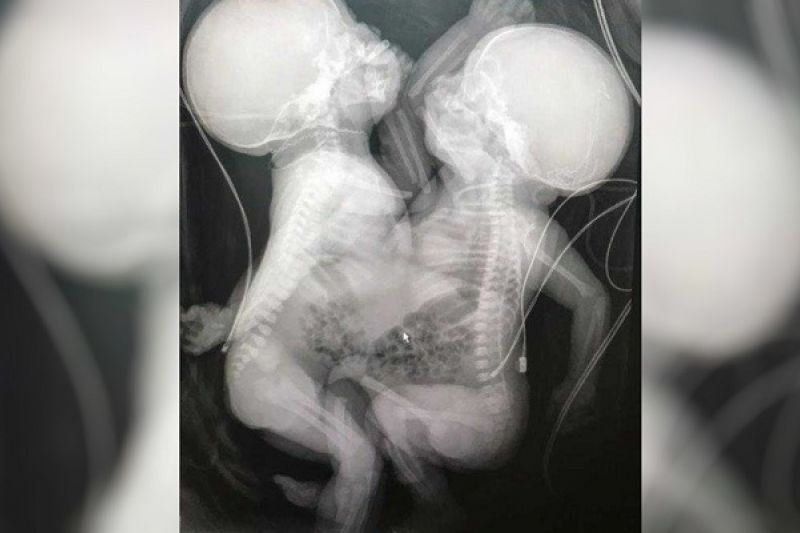

As recém-nascidas passaram pela cirurgia de separação na quinta-feira (23), um dia após o nascimento. A operação, que durou 4h30, foi feita em caráter de urgência porque uma das gêmeas tem um problema cardíaco e precisará passar por outra operação, ainda sem data definida.

De acordo com a equipe médica o HMI, do ponto de vista técnico, a cirurgia foi concluída com "êxito". Elas nasceram na manhã de quarta-feira (22) na 37ª semana de gestação, com 4,785 kg, unidas pelo tórax e abdômen. Ambas compartilhavam o fígado, que foi dividido na separação.